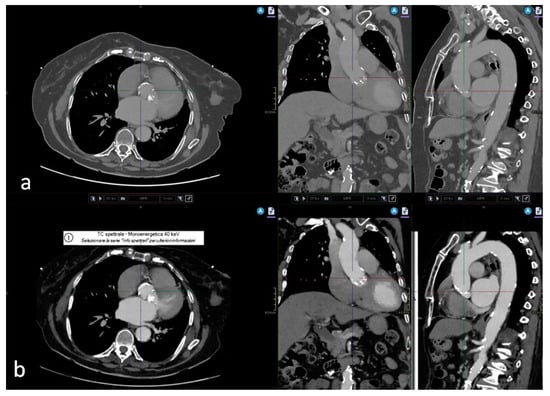

2. Materials and Methods

3. Results

3.2. Quantitative and Qualitative Assessment